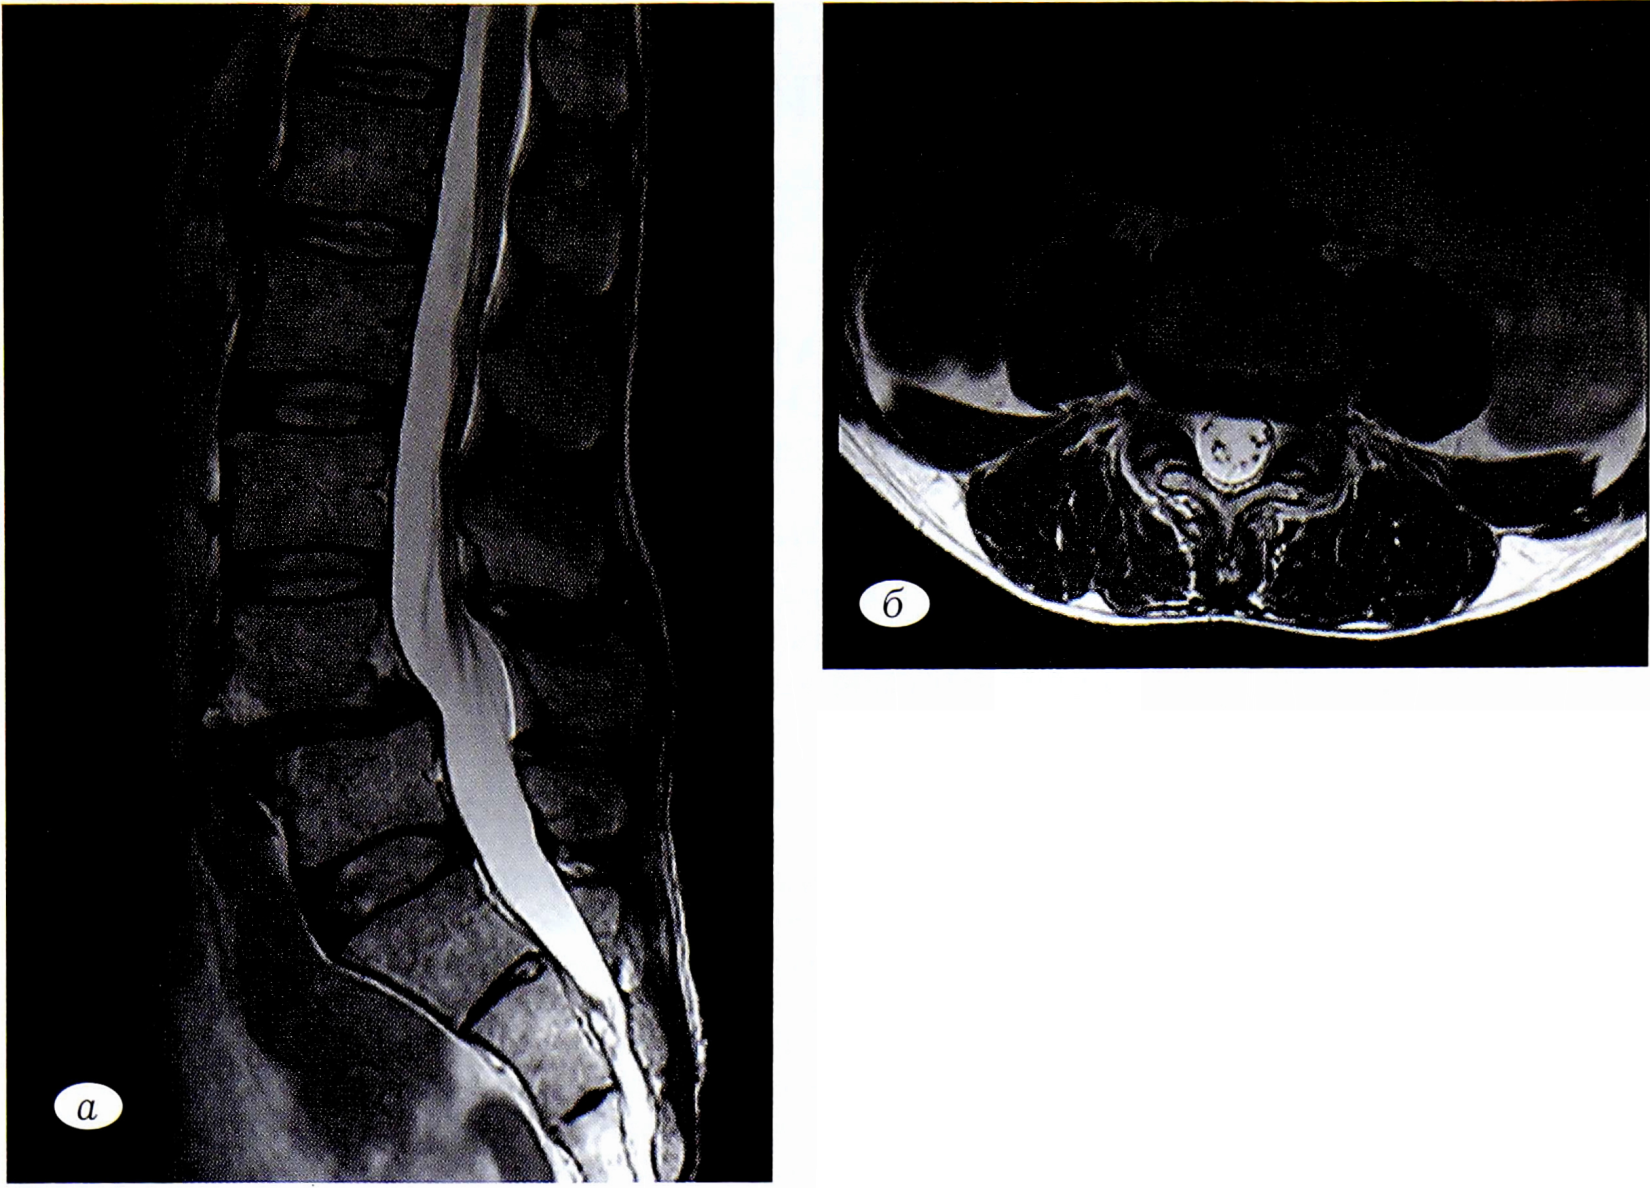

По результатам МРТ поясничного отдела позвоночника, выполненной через 6 мес в плановом порядке (рис. 5): состояние после оперативного вмешательства в сегменте LIѴ-LV, признаков дополнительной компрессии структур позвоночного канала не выявлено.

Рис. 5. Послеоперационные снимки МРТ поясничного отдела позвоночника пациента Ш.: а — Т2-ВИ, сагиттальная проекция; б — Т2-ВИ аксиальная проекция на уровне межтелового пространства LIV-LV.

Fig. 5. Postoperative MRI images of the lumbar spine of the patient Sh.: a — T2-VI, sagittal projection; b —T2-VI axial projection at the level of interbody space LIV-LV.